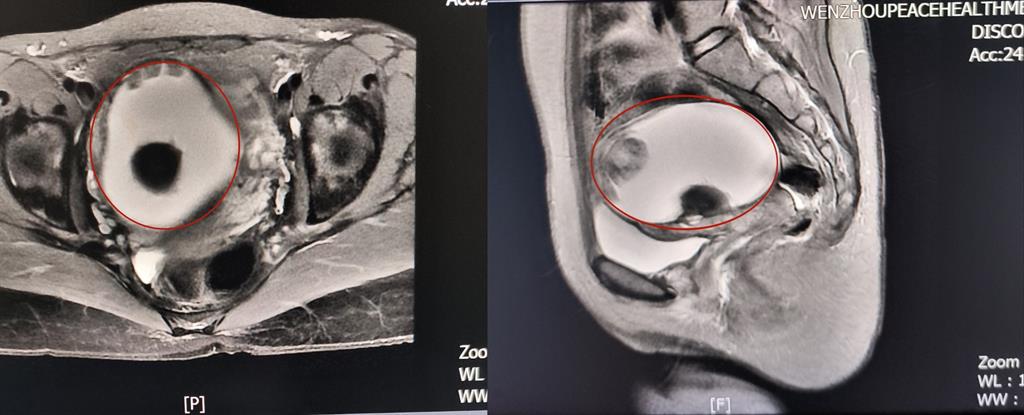

前不久,溫州某高校外籍教師A女士來到和平國際醫(yī)院體檢與健康管理中心進(jìn)行深度體檢。B超提示“子宮右側(cè)附件區(qū)囊性塊,大小約82*79*88mm”和平國際醫(yī)院婦科主任醫(yī)師方軼萍發(fā)現(xiàn),A女士還有三項(xiàng)腫瘤標(biāo)志物數(shù)據(jù)超標(biāo)(甚至高出正常值兩倍)。

卵巢腫瘤?為進(jìn)一步明確診斷,A女士在方主任建議下做了增強(qiáng)磁共振,影像結(jié)果提示:盆腔右側(cè)團(tuán)塊狀占位伴多發(fā)成熟脂肪成分大小約89*100*71mm,考慮畸胎瘤可能性大。謎團(tuán)逐漸解開,原來那個(gè)“怪胎”可能是畸胎瘤在作祟。

回家考慮后,A女士決定來和平國際醫(yī)院手術(shù)治療。“畸胎瘤大部分是良性,而且患者未婚未育,評估后我們決定采用微創(chuàng)的治療方案——腹腔鏡下畸胎瘤剝除術(shù)。”方主任講到,這樣不僅創(chuàng)傷小,還能保護(hù)患者的生育能力。

因腫物與周圍組織粘連致密暴露困難,這極考驗(yàn)主刀醫(yī)生的經(jīng)驗(yàn)和專業(yè)技術(shù)。為避免腫瘤破裂及血管損傷,和平國際醫(yī)院婦科團(tuán)隊(duì)主任醫(yī)師方軼萍、副主任醫(yī)師周婷在腹腔鏡下精細(xì)操作,完整切除囊腫,術(shù)中快速冰凍病理檢查結(jié)果證實(shí):成熟型囊性畸胎瘤(良性)。